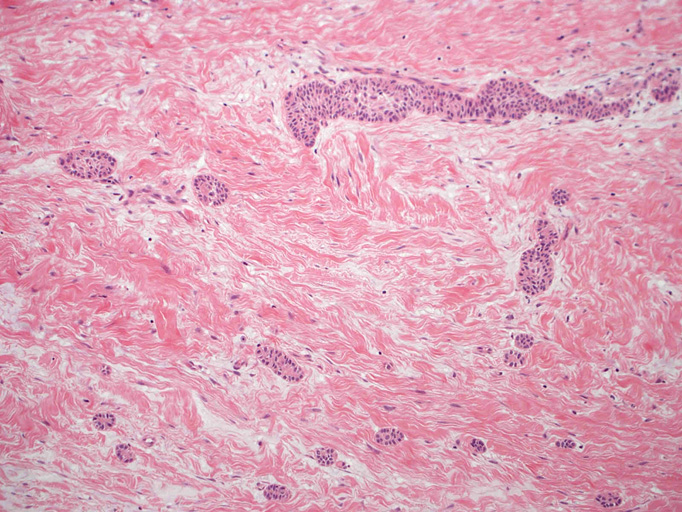

嚢胞性病変の壁を裏装する上皮はspongiosisあるいはintraepithelial edemaと棘細胞への分化を示す。7-15層の上皮で, 基底細胞はpalisadingを呈している。上皮脚は平坦で角化は認められない(Fig.01-Fig.04)。嚢胞壁はわずかにmyxoidな成分を伴うdensな膠原線維性間質からなり, その中に小さな胞巣状の歯原性上皮巣が散在している。核分裂像は認められない(Fig.05, 06)。

Fig.05Fig.06Fig.07Fig.08